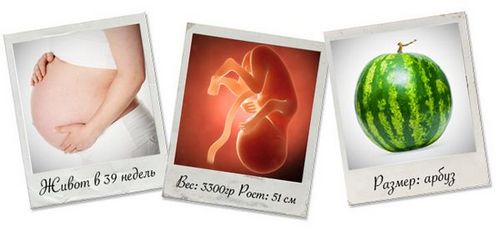

На 39 тижні вага плода становить близько 3300 гр, а його зріст дорівнює приблизно 51 см. У вашому животі живе малюк розміром з кавун.